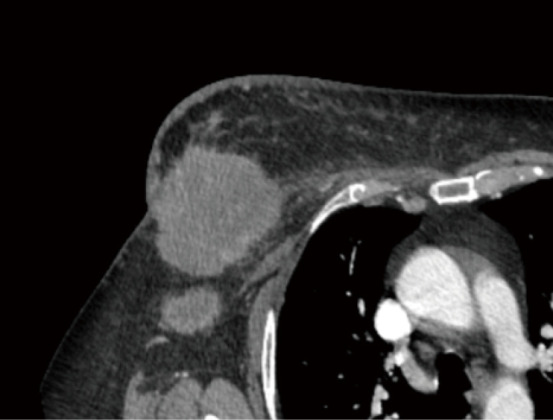

Key content and findings: Improved imaging techniques, with positron emission tomography-computed tomography and magnetic resonance imaging, have led to increase in the identification of IM lymphadenopathy, yielding surgical staging of the IM nodes nearly obsolete. While IM nodal metastases may play a role in overall survival (OS), it has not been demonstrated to be an independent risk factor for increased locoregional recurrence. IM nodal irradiation (IMNI) therapy has been a mainstay in the treatment of IM disease in the context of breast cancer. IMNI has demonstrated improvement in OS and risk of distant recurrence. Wide variations in radiation practices for patients with IM lymphadenopathy exist internationally, highlighting the lack of clear data driven consensus guidelines.